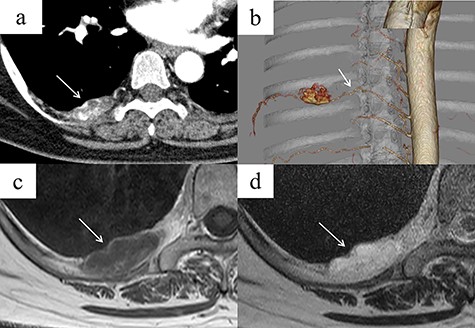

A 48-year-old woman was brought to our hospital owing to loss of consciousness; she had no major disease history, an unremarkable physical examination and normal laboratory findings. Contrast-enhanced chest CT revealed a mass 35 mm in diameter, with heterogeneous contrast, in the right posterior mediastinum at the thoracic T7–T8 level (Fig. 1a). The mass was not considered to have extended into the surrounding tissues or the spinal canal. An intercostal arterial feeder to the mass was observed on 3D-CT (Fig. 1b). Magnetic resonance imaging (MRI) revealed low T1-weighted and high T2-weighted signals in the mediastinal mass. A high-signal area on T1-weighted MRI suggested a fatty component inside the mass (Fig. 1c and d). We suspected a schwannoma or hemangioma or lipoma preoperatively and planned surgical resection Based on evidence of hypervascularity of the mass, preoperative embolization was planned to prevent unexpected massive intraoperative bleeding. On angiography, a feeding vessel from the right eighth intercostal artery to the mass was identified, with associated staining of the mass (Fig. 2a). We selectively embolized this feeding vessel using gelatin, resulting in the associated disappearance of staining (Fig. 2b). On Day 1 post-embolization, the tumor was resected using VATS. Intraoperatively, a soft mass with a fatty component and no surrounding tissue invasion was confirmed (Fig. 2c). The tumor was completely resected, in 96 min with minimal intraoperative blood loss. Microscopy revealed mature adipocytes, multiple small vessels and no malignancies (Fig. 2d). Histopathology confirmed a posterior mediastinal angiolipoma. The patient’s post-operative course was uneventful, with no recurrence at the 6-month follow-up post-surgery.

(a) Contrast-enhanced chest CT showing a right posterior mediastinal mass measuring 35 mm in diameter with heterogeneous contrast at the T7–T8 level, without extension into the spinal canal (arrow). (b) Three-dimensional reconstruction CT showing a feeding artery to the mass arising from the intercostal artery (arrow). (c, d) MRI showing low signal intensity on T1-weighted images but a bright signal on T2-weighted images (arrows). A high-signal area on T1-weighted MRI is suggestive of a fatty component inside the tumor. (c) T1-weighted image. (d) T2-weighted image.